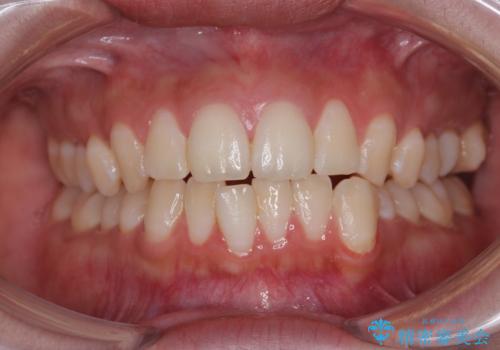

- 下の前歯のデコボコと、口元の突出感を改善したいと来院された患者様です。

上下左右の第一小臼歯を抜歯して、目立ちにくいワイヤー装置で矯正を行いました。

上下の保定用マウスピースの他に、デコボコの強かった下顎前歯にはワイヤーで保定をしています。